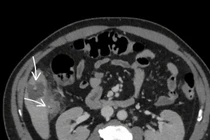

Tại đây, qua kết quả chẩn đoán hình ảnh các bác sĩ phát hiện dị vật hình dạng giống tăm tre đã xuyên thủng thành đại tràng, gây viêm phúc mạc khu trú.

Dị vật là tăm tre trong bụng bệnh nhân/ Ảnh SKĐS